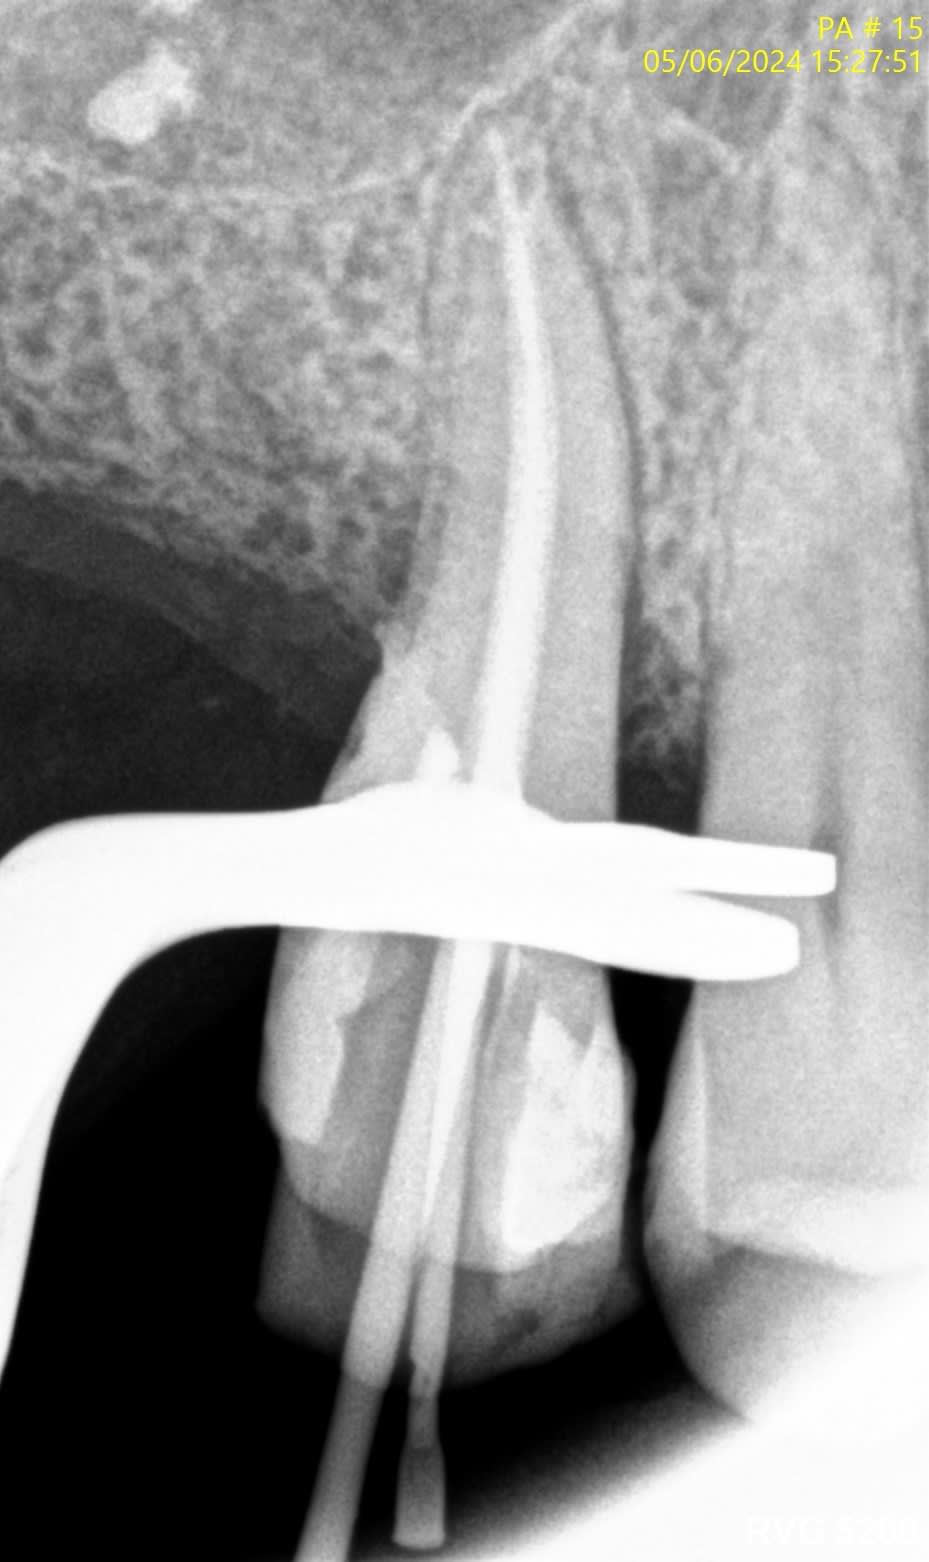

Voici quelques radio pour illustrer...

J’ai l’impression que sur les radios que tu montres il y a des fractures verticales.